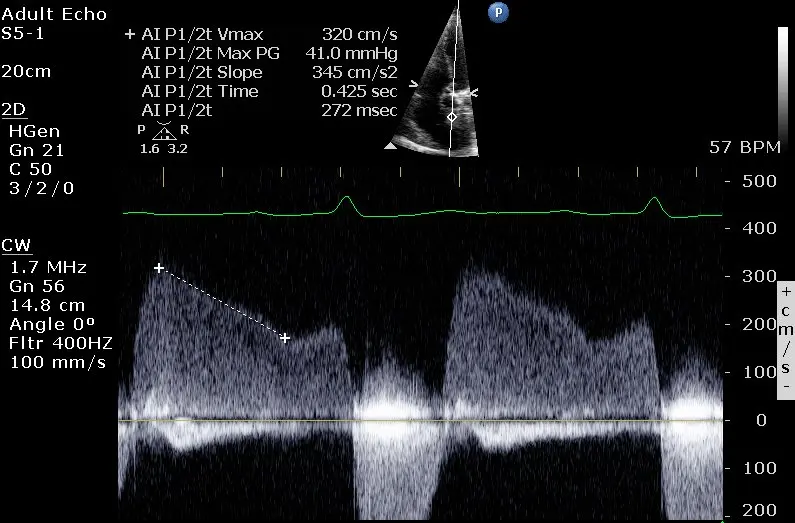

Pressure Half Time (PHT)

Mitral Valve Area (MVA) from PHT

In the above Doppler tracing, is 2 m/s. This example also illustrates the ‘a-dip’ that can sometimes be seen with Aortic Regurgitation.